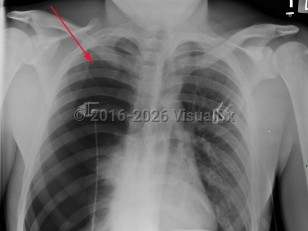

Spontaneous pneumothorax

Spontaneous pneumothorax (SP) is caused by the introduction of air between the visceral and parietal pleura, typically as the result of trauma. SP can be classified as either primary or secondary. The presence or absence of lung disease distinguishes the primary form from the secondary form. Primary SP (PSP) lacks underlying lung disease, whereas secondary SP (SSP) patients have a preexisting condition such as chronic obstructive pulmonary disease (COPD; a majority of cases), cystic fibrosis, pulmonary infection, interstitial lung disease (especially histiocytosis and sarcoidosis), AIDS, neoplasms, or drug use.

The size of the pneumothorax, rate of development, and underlying clinical status determine the clinical presentation. Those with a mild PSP may not seek care, while those with SSP present acutely. The range of signs and symptoms include acute pleuritic chest pain (localized to the side of the pneumothorax), dyspnea, decreased breath sounds, tachypnea, tachycardia, hyperresonance, unilaterally decreased lung sounds, or acute decompensation.

Tension pneumothorax (TP), while rare, may result from an SP. TP, a life-threatening condition, is caused by pressurized air in the pleural space that displaces mediastinal structures and compromises cardiopulmonary function.